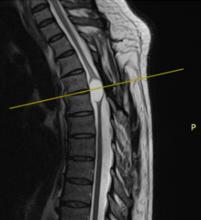

Acute post-surgical pneumocephalus is frequent in patients with cranioencephalic pathology operated on in the supine and prone position. The distribution and degrees of pneumocephalus may be related to sex, the type of cranioencephalic pathology, and the depth of the surgical lesion.